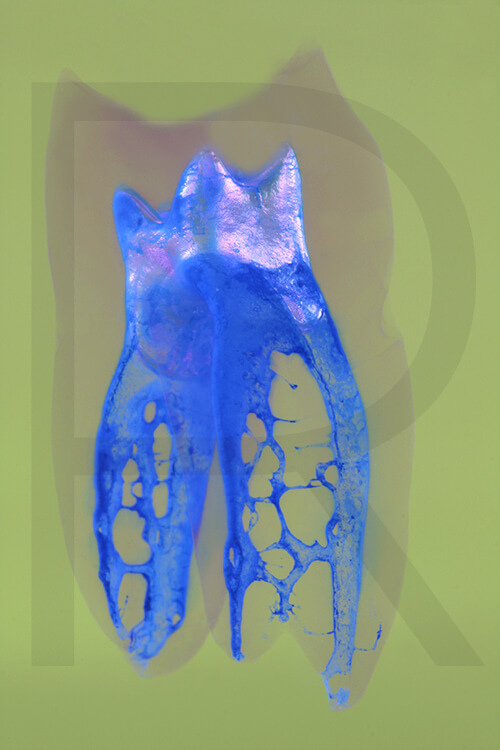

Bildauswahl Pop Art

- Foto hinter 3mm Acrylglas, rahmenlos

- hochwertige, unsichtbare Aufhängung, "schwebend“

- Hoher UV-Schutz für lang anhaltend strahlende Farben

- Bruchsicher und leichter als Glas

- Beeindruckende Farben und brilliante Tiefenwirkung

- Druck erfolgt ohne Wasserzeichen

- Bildgröße Variante 1: 90 x 120 cm

- Preis auf Anfrage, zuzüglich 20,90 Euro Versand & Porto innerhalb Deutschlands, weiterer Versand auf Anfrage

- Bildgröße Variante 2: 90 x 90 cm, quadratisch

- Preis auf Anfrage, zuzüglich 20,90 Euro Versand & Porto innerhalb Deutschlands, weiterer Versand auf Anfrage

- Bildgröße Variante 3: 60 x 120 cm, Hochformat

-

Preis auf Anfrage, zuzüglich 20,90 Euro Versand & Porto innerhalb Deutschlands, weiterer Versand auf Anfrage

Wenn Sie Interesse an den Fotos transparenter Zahnpräparate haben, bieten wir hier die Möglichkeit einige Versionen als Acrylbilder (alle Detailinformationen zu Größe und Preis siehe obige Auswahl) zu bestellen.

Die Bilder sind nicht nur zur Praxisverschönerung geeignet sondern auch eine wertvolle Unterstützung bei der Patientenberatung vor endodontischen Behandlungen.